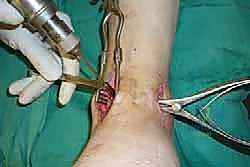

خطوات جراحة تثبيت مفصل الكاحل الأمامي بالتفصيل (Step-by-Step Surgical Procedure)

تُجرى العملية تحت التخدير العام أو النصفي (الشوكي)، وتستغرق عادةً بين ساعتين إلى ثلاث ساعات، وتتطلب دقة ومهارة فائقتين. إليكم الخطوات الجراحية كما ينفذها الأستاذ الدكتور محمد هطيف:

1. الوضعية والشق الجراحي (Positioning and Incision)

يستلقي المريض على ظهره (Supine position). يتم استخدام عاصبة (Tourniquet) حول الفخذ لتقليل النزيف وتوفير رؤية واضحة. يقوم الدكتور هطيف بإجراء شق طولي أمامي فوق مفصل الكاحل، عادة بين وتر العضلة الظنبوبية الأمامية (Tibialis Anterior) ووتر العضلة الباسطة الطويلة لإصبع القدم